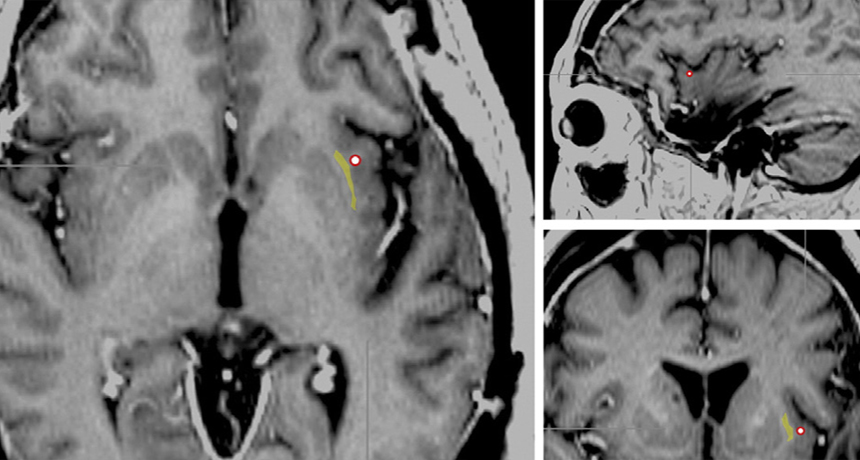

OFF SWITCH  An electrode (red circle) used to stimulate a brain site near an epileptic woman’s claustrum (highlighted in yellow) appears on these brain scans. When the electrode was turned on, she appeared to lose consciousness.

M. Koubeissi et al/Epilepsy & Behavior 2014